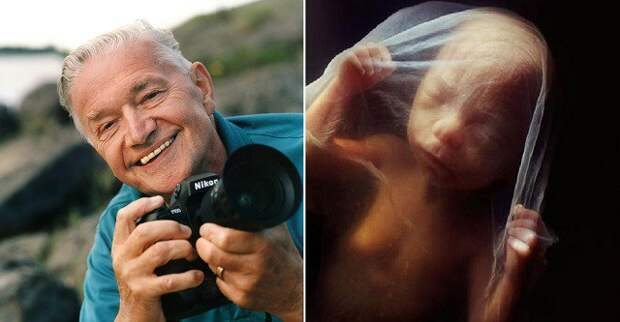

Работы знаменитого фотографа Леннарта Нильссона

Раздел: Фотопанорама